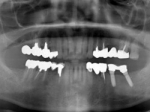

術前レントゲン

術前口腔内(正面観)